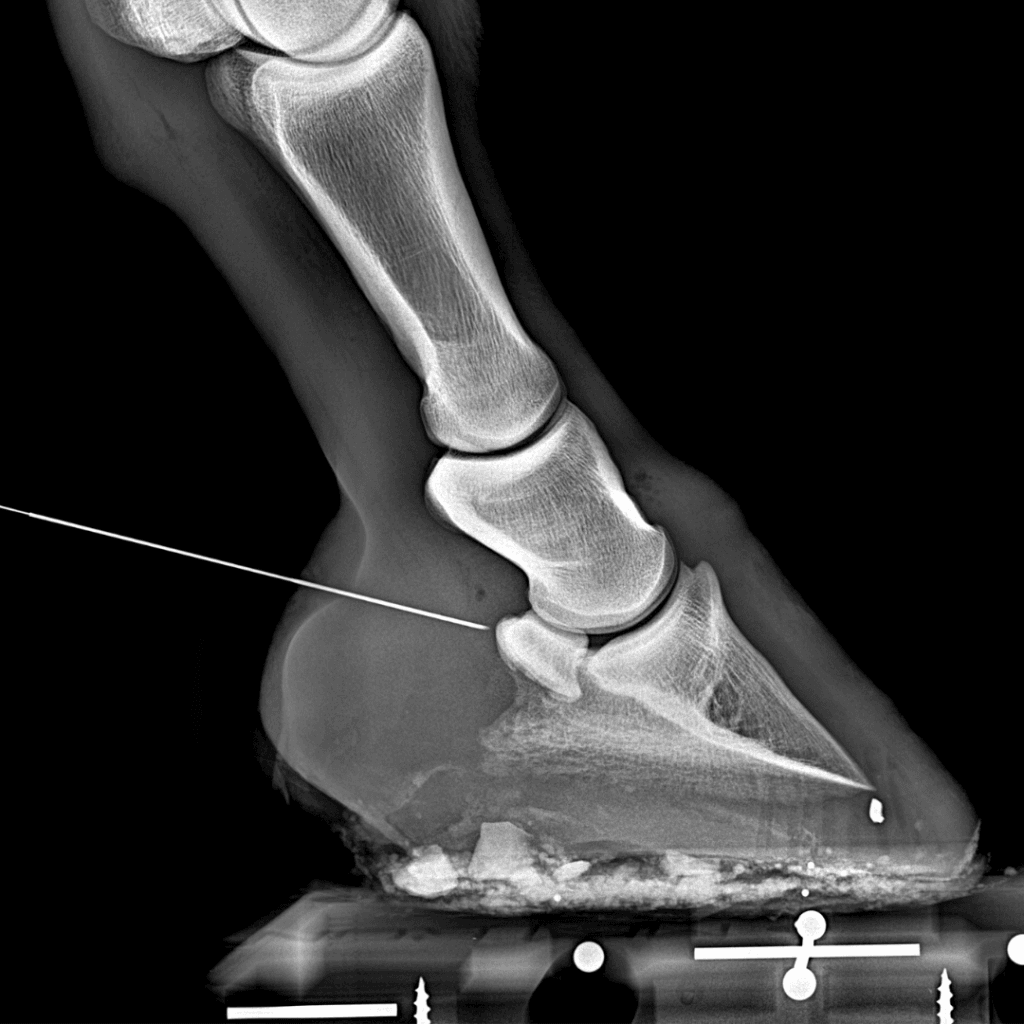

Experto en exámenes pre-compra, diagnóstico por imagen y odontología equina

Contamos con el último equipamiento para la realización de pruebas médicas, radiografías, ecografías, tratamientos de plasma...

A continuación estuve durante un año adquiriendo formación en medicina deportiva y diagnóstico de cojeras con D. Juan Roldán Romero (Equinuvi) en Córdoba. Posteriormente realicé un internado de un año de duración en el Servicio de Clínica Equina del Centro Policlínico Veterinario Raspeig (Alicante) junto a D. Salvador Termes y D. Manuel A. Rodriguez.